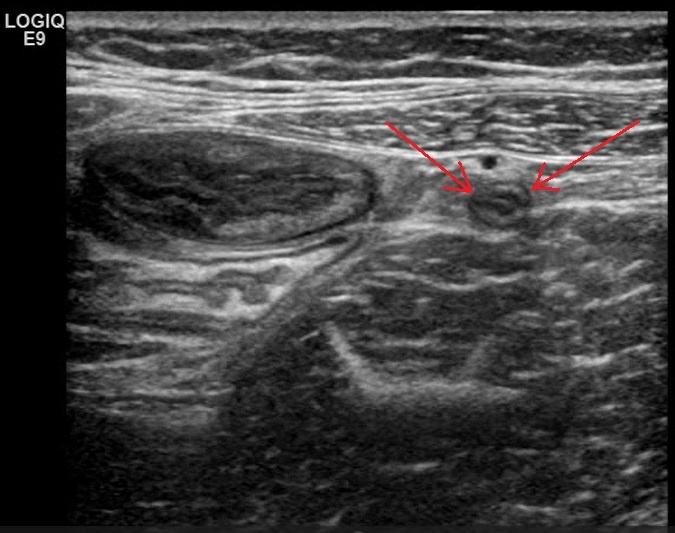

Рядом с воспаленной кишкой лоцируются единичные лимфатические узлы, не увеличены (размеры не превышают 10 мм) но с резко сниженной эхогенностью и отсутствием корково-мозговой дифференцировки (признаки мезаденита)

Рис. 07 - визуализация брыжеечных лимфатических узлов